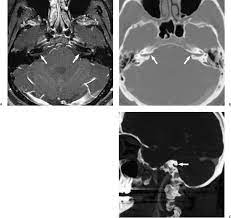

Surgical Exposure Of The Internal Auditory Canal Through The Retrosigmoid Approach With Semicircular Canals Anatomical Preservation

Head and neck anatomy is important when considering pathology affecting the same area. Choose from 500 different sets of flashcards about anatomy and physiology on quizlet. Radiological anatomy is crucial for radiologists and forms the base for learning radiology. Tineke willems and marieke hazewinkel.